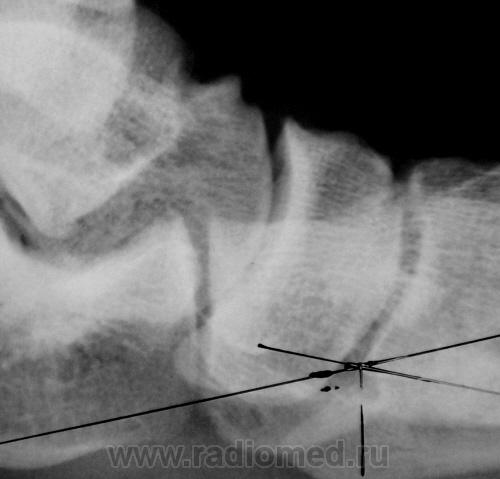

Первичная постановка на военный учет. Направлен из военкомата для определения наличия продольного плоскостопия и наличия/отсутствия деформирующего артроза в суставах среднего отдела стопы. Данные рентгенометрии свидетельствуют о наличии продольного плоскостопия 2-3 ст.

Валентин Львович! Наш военный рентгенолог всегда пытается начать построение угла из глубины клино-ладьевидного сочленения, старается обязательно достигнуть суставную щель. Ваша иллюстация о том же. Насколько это правильно?

Это регламентировано последним разъяснением МО.

ОА т/л суставов 1ст. Слева выражена таранная шпора. У военных нет 2-3 степени. Либо 2, либо3.

По всей видимости, определяющим должен быть угол, так как "высота" может разниться у обладателя ноги 39 и 46 размеров....

Кроме того, высота, весьма зависит от колебаний фокусного расстояния, при котором произведен снимок...